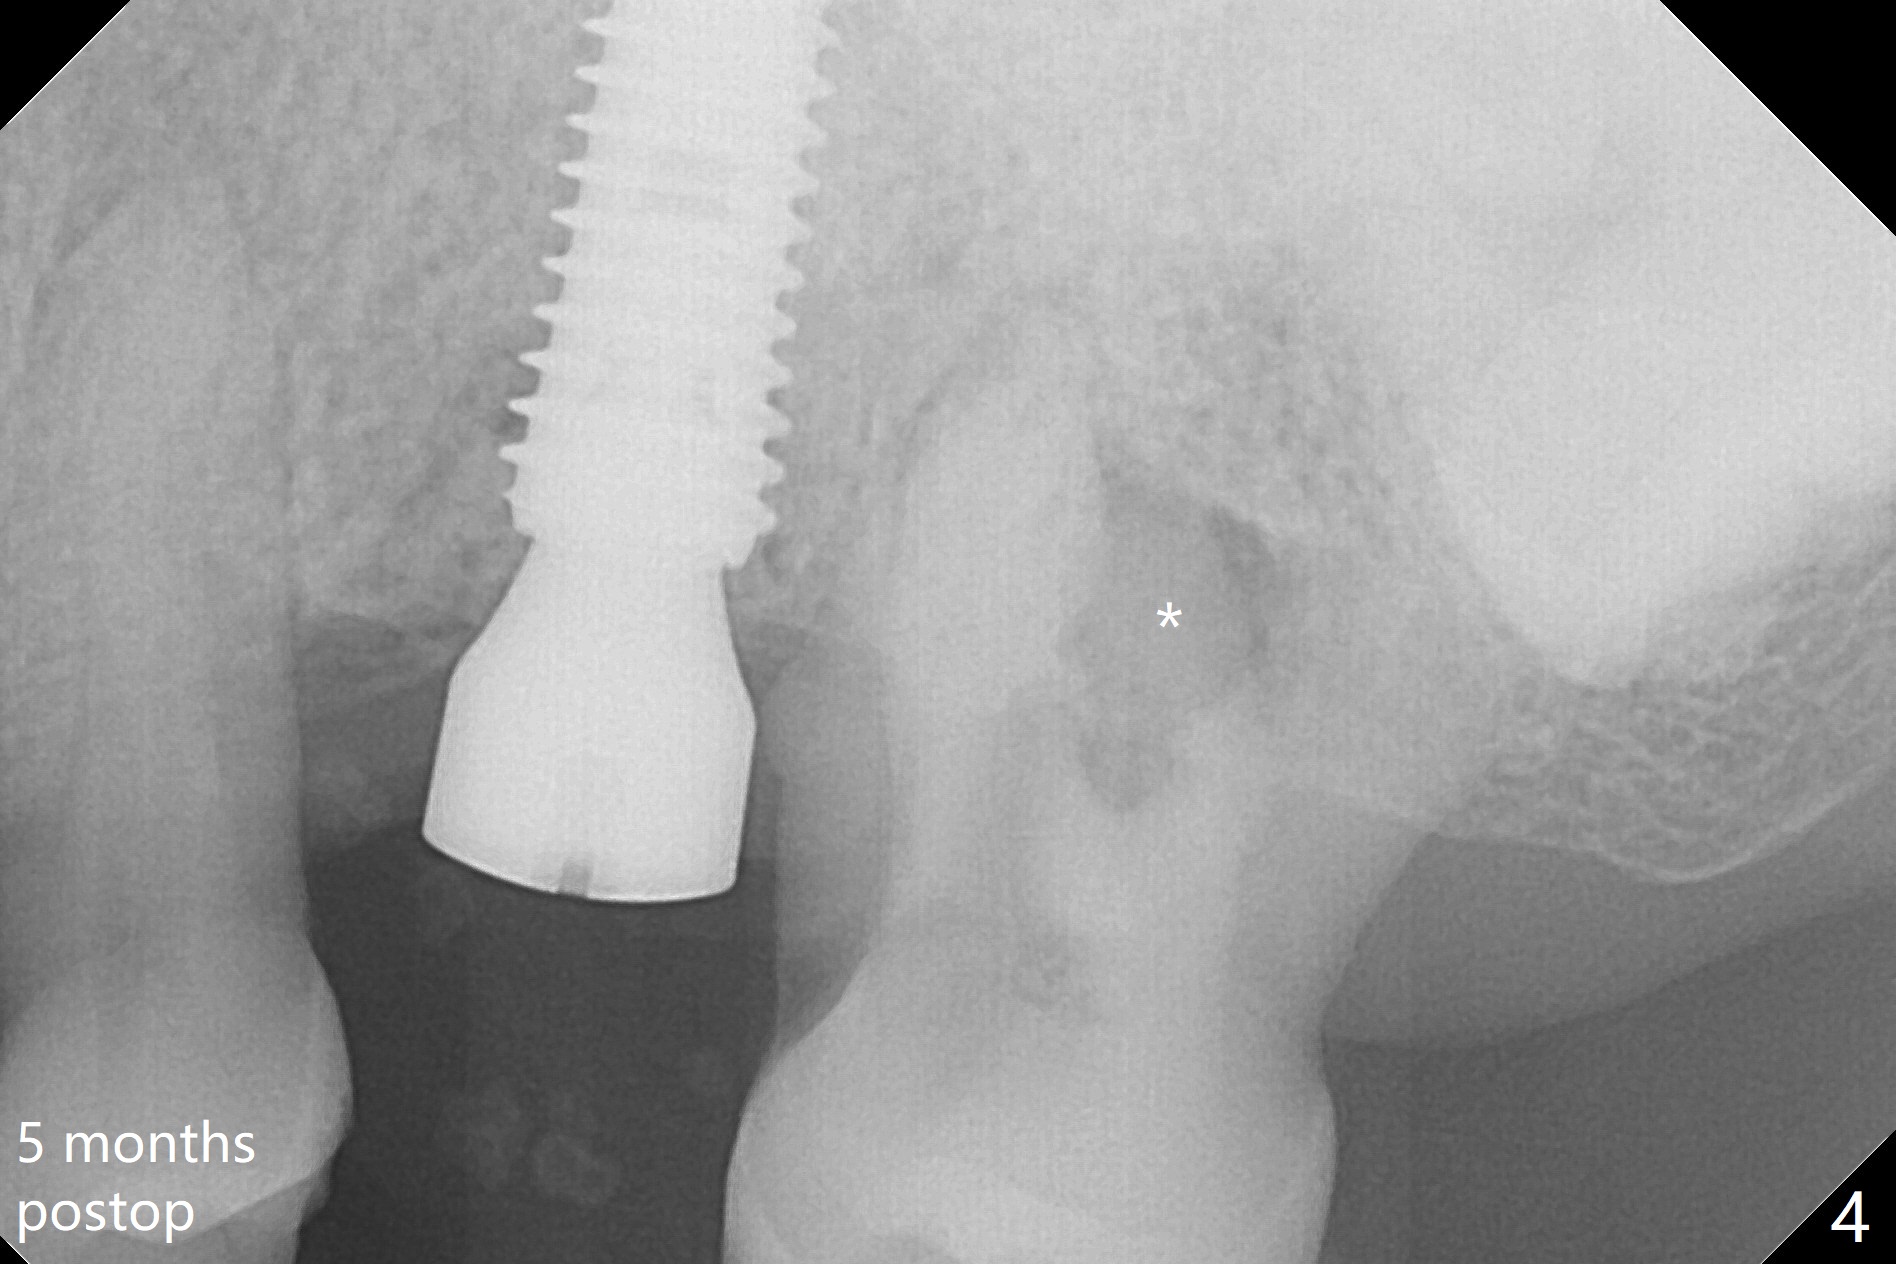

The patient is extremely nervous about implant placement at #14. Access is obtained with a 4 mm tissue punch, which appears to be the least traumatic. Since the gingiva is ~ 5 mm thick, vision is poor and it is difficult to change osteotomy buccally. It seems a 6 mm tissue punch is more appropriate for this case. The initial osteotomy depth is 14 mm (Fig.1). Since the tooth #15 is nonsalvageable because of furca caries and bone loss (Fig.1 *), the distal osteotomy at #14 is apparently acceptable. When a 5x13 mm implant is placed with >50 Ncm (Fig.2), the implant is subcrestal clinically except palatal (osteotomy not buccal enough), which is consistent with bitewing view (Fig.3). A 5.5x5 mm healing abutment is placed. Surprisingly the fearful patient does not experience any pain. Tissue punch is an atraumtic measure. A larger one (6 mm) allows more room to change osteotomy. The access can be closed with larger healing abutment. If this implant fails due to periimplantitis, it is due to palatal placement with too large the implant (5 mm vs. 4 mm at #3). Palpate the bone prior to changing next large drill when performing a flapless procedure. The implant seems to be osteointegrated 5 months postop; the furca caries (Fig.4 *) is taken care of before impression with a 4.5x5(4) mm abutment. Distal caries of the tooth #13 is found 10 months post cementation (Fig.5). Strict oral hygiene for prevention should have been given after composite for the furca of the tooth #15 (*).